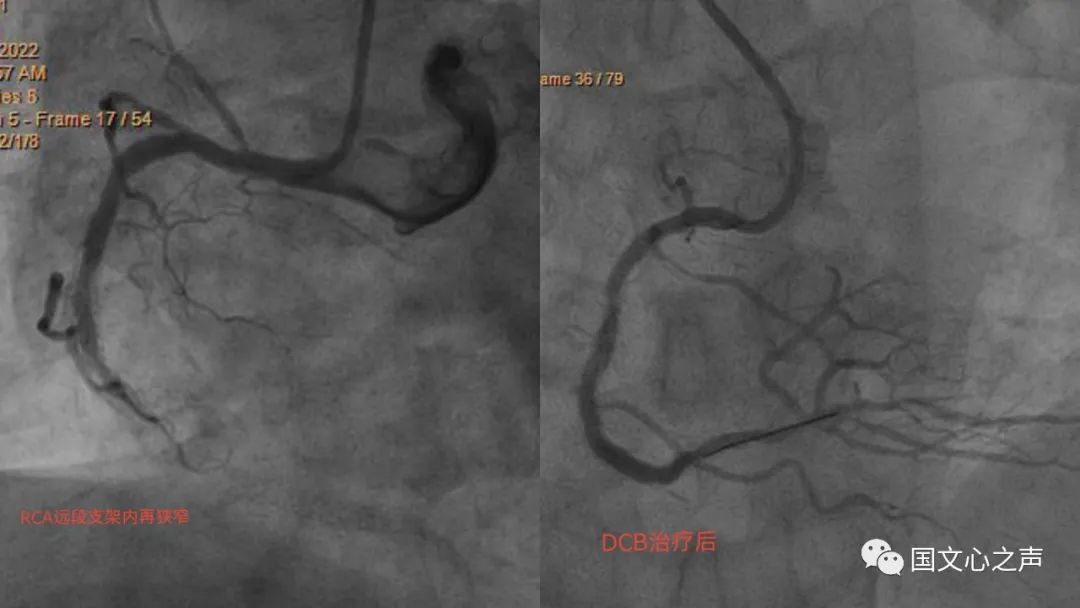

李主任了解到張叔叔的來意,告知藥物涂層球囊的適應(yīng)癥,便安排其做了冠脈造影,造影結(jié)果提示原來的右冠脈的支架完全被堵死,這正是藥物涂層球囊治療的適應(yīng)證,征得本人及家屬同意后在病變的支架內(nèi)先應(yīng)用后擴(kuò)張球囊,再應(yīng)用藥物涂層球囊,術(shù)后效果非常好!